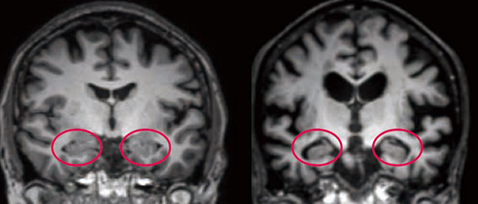

- 알츠하이머는 아밀로이드 베타 단백질과 타우 단백질의 이상 축적이 주요 원인입니다.